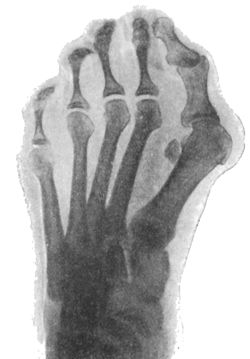

157.Radiogram of Hallux Valgus296

158.Radiogram of Hallux Varus or Pigeon-Toe298